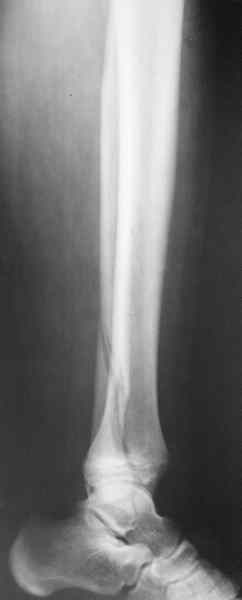

Если есть ЭОП, то перелом подходит для малоинвазивной фиксации. Репозиция суставного отдела (использовать репозиционные щипцы)и его фиксация стягивающими винтами чрезкожно, затем пластина медиально малоинвазивно, лучше метафизарная. Если не располагаете подходящим имплантом или непозволяют мягкие ткани, вполне возможно применить вместо платы Fix.Ex.

В приложении метафизарный перелом у ребёнка 14лет, с распространением линии перелома на зону роста.